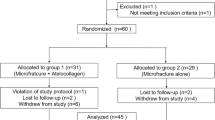

A single senior author treated 60 OLT patients (61 ankles) at Konkuk Medical Center using arthroscopic microfracture from 2009 to 2014. OLTs were confirmed using preoperative MRI and ankle arthroscopy. The inclusion criteria were patients with a diagnosis of OLT whose pain remained unresponsive to conservative management, including rest, splints, such medications as non-steroidal anti-inflammatory drugs, and physical therapy, for at least 6 months. Patients were included only if they agreed to undergo CTA at 6-month, 1-year, and 2-year follow-ups. Any psychotic disorders, diabetes, or immune diseases, e.g. rheumatoid arthritis, a previous history of ankle surgery, or a follow-up less than 6 months after surgery, were excluded. All the patients were instructed to undergo CTA post-operatively and to complete a survey during the follow-up period; a total of 42 patients (42 ankles) were enrolled.

A total of 26 men and 16 women with a mean age of 39.8 ± 15.7 years and a mean body mass index (BMI) of 25.6 ± 3.8 kg/m2 were included in the sample at the time of surgery. Twenty-one of the ankles of interest were on the right side. Thirty patients (71.4%) had evident previous trauma. All patients complained of more than one symptom, including chronic ankle pain, swelling, functional limitations, or weakness. The median duration of preoperative ankle pain was 20.0 months (range 6–120 months), and the median follow-up period was 13.0 months (range 6–54 months).

Nine patients had ten concomitant diseases at the time of surgery, including three cases of lateral ankle instability, three cases of sinus tarsi syndrome, one case of painful accessory navicular, one case of ankle soft tissue impingement, and two cases of tibial osteophytes. To eliminate confounding effects, these nine patients were excluded from the analysis of the relationships between the CTA findings and the clinical outcomes.

Post-operative ankle CTA was performed on 40, 18, and 10 ankles at 6 months, 1 year, and 2 years after the surgery, respectively. Clinical surveys were completed preoperatively and then post-operatively at 6 months, 1 year, and each year thereafter.

Correlation analyses were performed to correlate the AOFAS functional score and the VAS pain score with the thickness and repaired area of each affected lesion. Improvements in the AOFAS functional score and the VAS pain score, which followed a normal distribution, were assessed using a paired-sample T test. Radiographic changes at 6 months and 1 year after surgery were validated using the Wilcoxon test. Univariate analyses were performed using Pearson’s or Spearman’s correlations. For the analysis of the relationship between the thickness of repaired tissue and clinical scores, repaired tissue thickness grades of 0 and 1 were coded as “0”, whereas 2 and 3 were coded as “1”. For this correlative analysis, the clinical score at the final follow-up of each patient was used. Thus, the data from all 42 patients were analysed for correlations between tissue thickness determined by CTA and clinical outcomes. To detect the factors that affect tissue growth, a logistic regression analysis was performed on the same assumption. Patient sex, age, symptom duration, BMI, and trauma history were used as independent factors in this analysis; p values less than 0.05 were considered significant in all situations. To estimate the required sample size, the VAS pain score was used as the primary outcome and an attempt was made to distinguish differences of 0.5 in patients prior to surgery and at the final follow-up with a standard deviation of 0.5 points and an effect size of 1. Based on these parameters, the power analysis indicated that a sample size of 34 would provide 80% power to detect an effect of this magnitude (α = 0.05, β = 0.2).